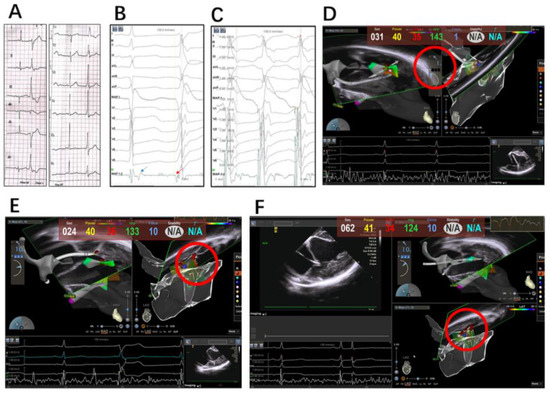

2.2. Electrophysiology Study, Mapping and Ablation

2.2.1. Intracardiac Echocardiography

2.2.2. Mapping and Ablation

4.1. Integration of Echocardiography and 3D Mapping